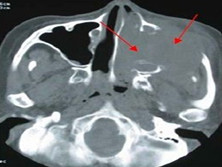

鼻窦恶性肿瘤

上颌窦恶性肿瘤早期,单侧脓血鼻涕;脸颊疼痛麻木;单侧进行性鼻塞;单侧上颌磨牙疼痛...